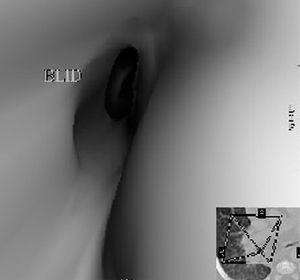

Se practica TC helicoidal multicorte observando un patrón micronodular difuso asociado a condensaciones en los segmentos 1 del lóbulo superior derecho, 6 y 9-10 del lóbulo inferior izquierdo con cavitaciones.

Tras administrar contraste intravenoso se identifican múltiples adenomegalias mediastínicas, de tamaño superior al centímetro de diámetro, en los espacios paratraqueal derecho, ventana aortopulmonar, subcarinal e hiliar izquierdo que realzan periféricamente con centro hipoatenuado (fig. 2).

Figura 2.Corte axial de TC tras la administración de contraste intravenoso. Adenomegalias subcarinal e hiliar izquierda con realce periférico y centro hipodenso por necrosis caseosa. Infiltrado en lóbulo inferior izquierdo cavitado y engrosamiento pleural asociado.